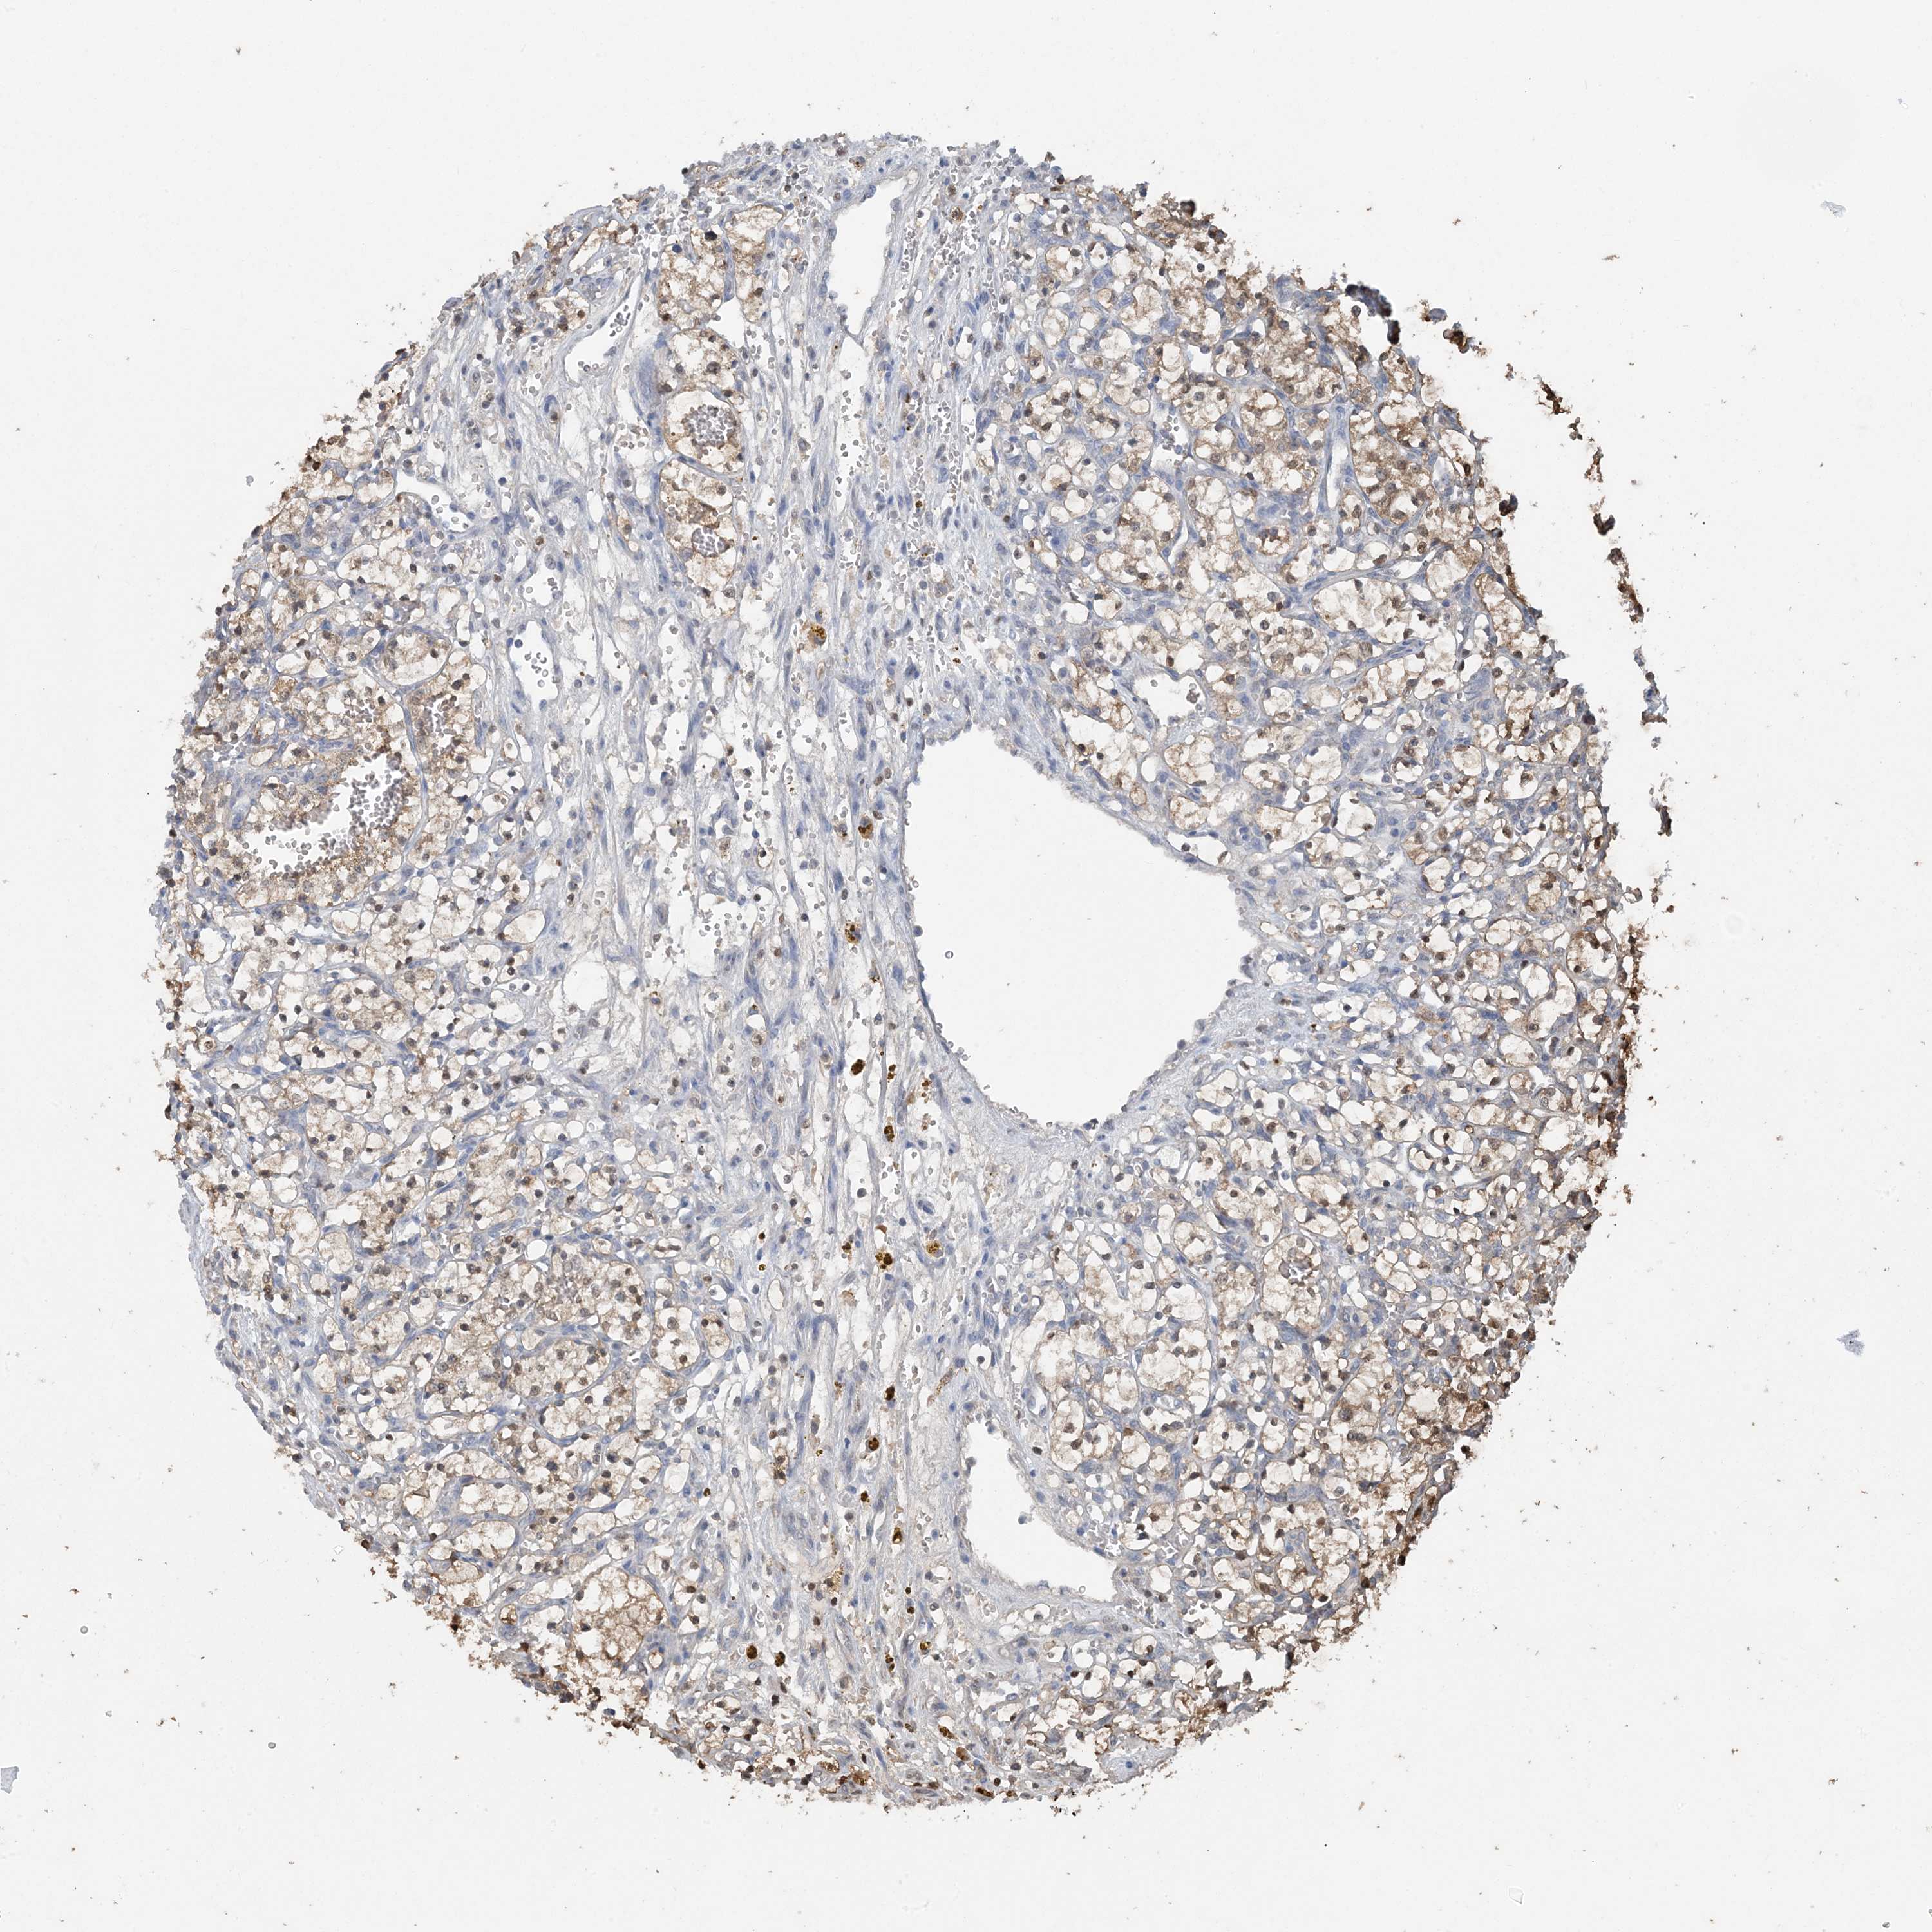

KIDNEY RENAL CLEAR CELL CARCINOMA (VALIDATION) - Interactive survival scatter ploti

The Survival Scatter plot shows the clinical status (i.e. dead or alive) for all individuals in the patient cohort, based on the same data that underlies the corresponding Kaplan-Meier plots. Patients that are alive at last time for follow-up are shown in blue and patients who have died during the study are shown in red.

The x-axis shows the expression levels (FPKM) of the investigated gene in the tumor tissue at the time of diagnosis. The y-axis shows the follow-up time after diagnosis (years). Both axes are complimented with kernel density curves demonstrating the data density over the axes. The top density plot shows the expression levels (FPKM) distribution among dead (red) and alive patients (blue). The right density plot shows the data density of the survived years of dead patients with high and low expression levels respectively, stratified using the cutoff indicated by the vertical dashed line through the Survival Scatter plot. This cutoff is automatically defined based on the FPKM cutoff that minimizes the p-score. The cutoff can be changed by dragging the vertical line or by entering a cutoff value in the square labeled "Current cut-off".

Under the Survival Scatter plot the p-score landscape (black curve; left axis) is shown together with dead median separation (red curve; right axis). Dead median separation is the difference in median mRNA expression between patients who have died with high and low expression, respectively. It is calculated as follows: median FPKM expression of dead patients with high expression - median FPKM expression of dead patients with low expression. This is intended to aid the user in visually exploring custom cutoffs and the associated p-scores and dead median separation.

Individual patient data is displayed and can be filtered by clicking on one or more of the category buttons on the top of the page. Categories describing expression level and patient information include: high, low, alive, dead, female, male and tumor stages. The scale of the x-axis can be toggled between linear and log-scale by clicking on the "x log" button. Mouse-over function shows TCGA ID, patient information and mRNA expression (FPKM) for each patient.

& Survival analysisi

Kaplan-Meier plots summarize results from analysis of correlation between mRNA expression level and patient survival. Patients were divided based on level of expression into one of the two groups "low" (under cut off) or "high" (over cut off). X-axis shows time for survival (years) and y-axis shows the probability of survival, where 1.0 corresponds to 100 percent.

HIKESHI is potential prognostic, high expression is unfavorable in Kidney Renal Clear Cell Carcinoma (validation)

Best expression cut offi

Based on the FPKM value of each gene, patients were classified into two groups and association between prognosis (survival) and gene expression (FPKM) was examined. The best expression cut-off refers the FPKM value that yields maximal difference with regard to survival between the two groups at the lowest log-rank P-value. Best expression cut-off was selected based on survival analysis .

When clicking on this number, the vertical dashed line indicating cut-off, the interactive survival plot, and the Kaplan-Meier curve will be adjusted to show results based on the best expression cut-off.

: 26.78

Median expressioni

Median expression refers to the median FPKM value calculated based on the gene expression (FPKM) data from all patients in this dataset. When clicking on this number, the vertical dashed line indicating cut-off, the interactive survival plot, and the Kaplan-Meier curve will be adjusted to show results based on the median expression.

: N/A

Median follow up timei

Median follow up time refers to the median time (years) after diagnosis with this type of cancer, based on clinical data from all patients in this dataset.

P scorei

Log-rank P value for Kaplan-Meier plot showing results from analysis of correlation between mRNA expression level and patient survival.

N/A

5-year survival highi

5-year survival for patients with higher expression than the expression cutoff.

For melanoma and glioma, 3-year survival is shown.

5-year survival lowi

5-year survival for patients with lower expression than the expression cutoff.

TCGA RNA samplesi

RNA-seq data is reported as average FPKM (number Fragments Per Kilobase of exon per Million reads), generated by the The Cancer Genome Atlas (TCGA) .

Normal distribution across the dataset is visualized with box plots, shown as median and 25th and 75th percentiles. Points are displayed as outliers if they are above or below 1.5 times the interquartile range. FPKM values of the individual samples are presented next to the box plot.

Average pTPM 21.2

Number of samples 100